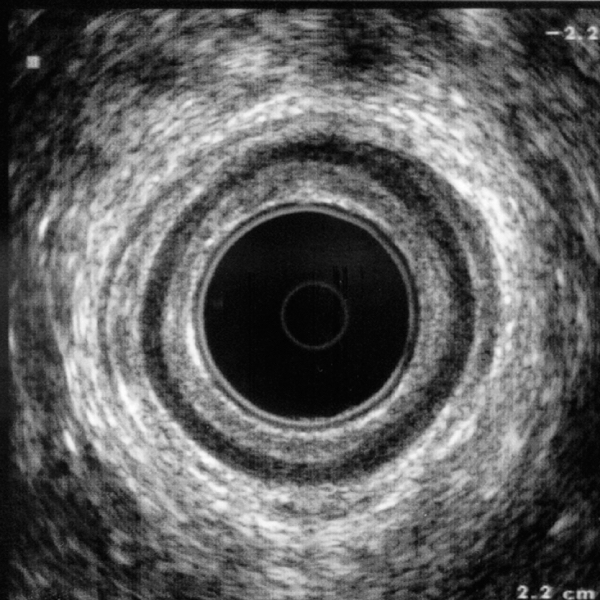

Estudio mexicano retrospectivo sobre la incidencia de enfermedades anorrectales diagnosticadas mediante ultrasonido anorrectal, realizado en el Hospital General Regional No. 58 del IMSS en León, Gto.